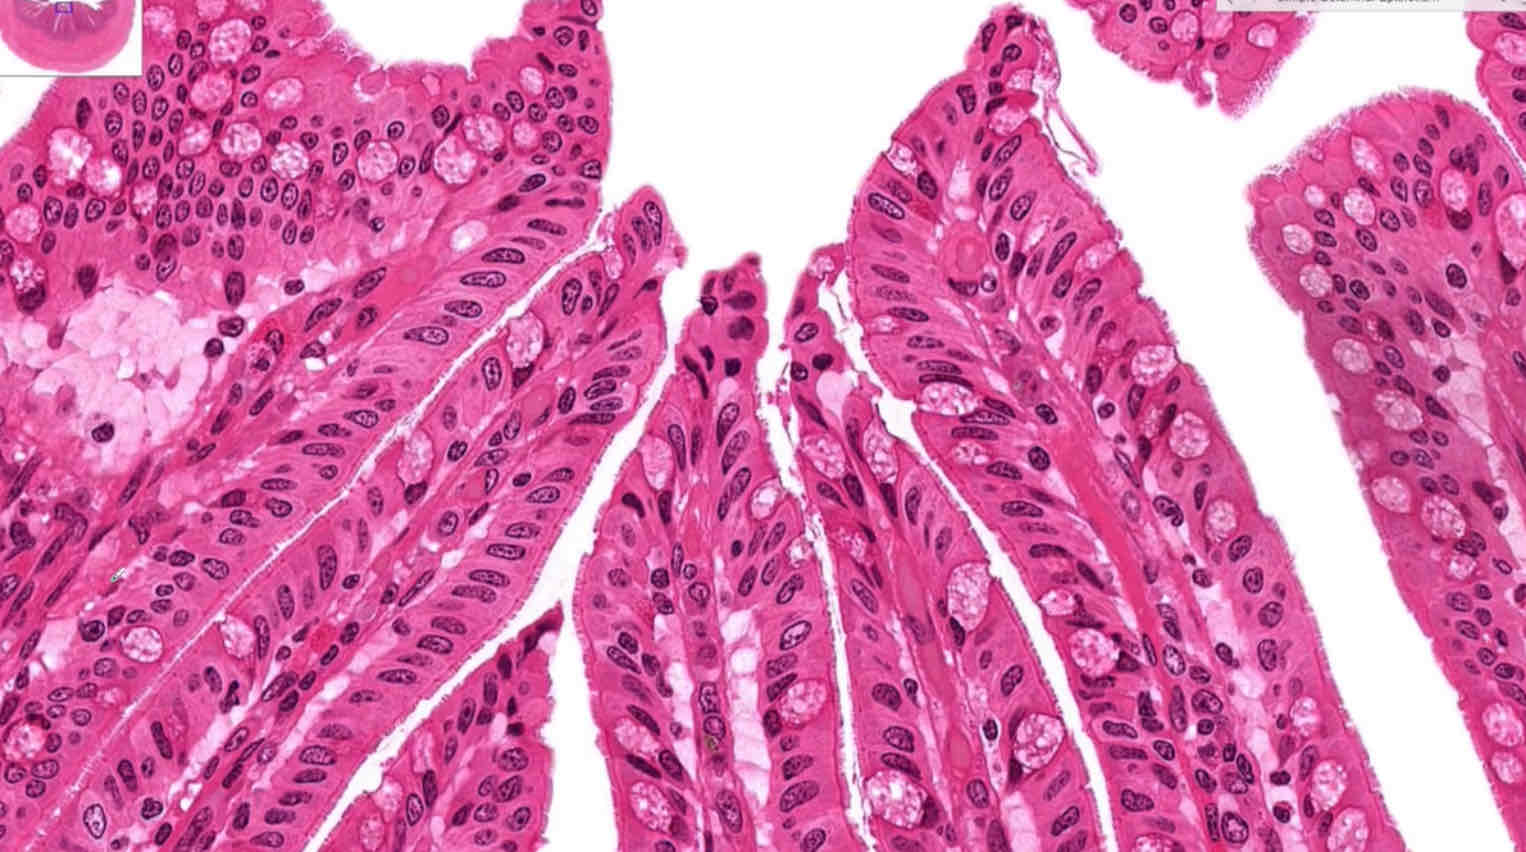

Simple columnar epithelium

Location of simple columnar epithelium

Intestinal tract

Function of simple columnar epithelium

Absorption, secretion